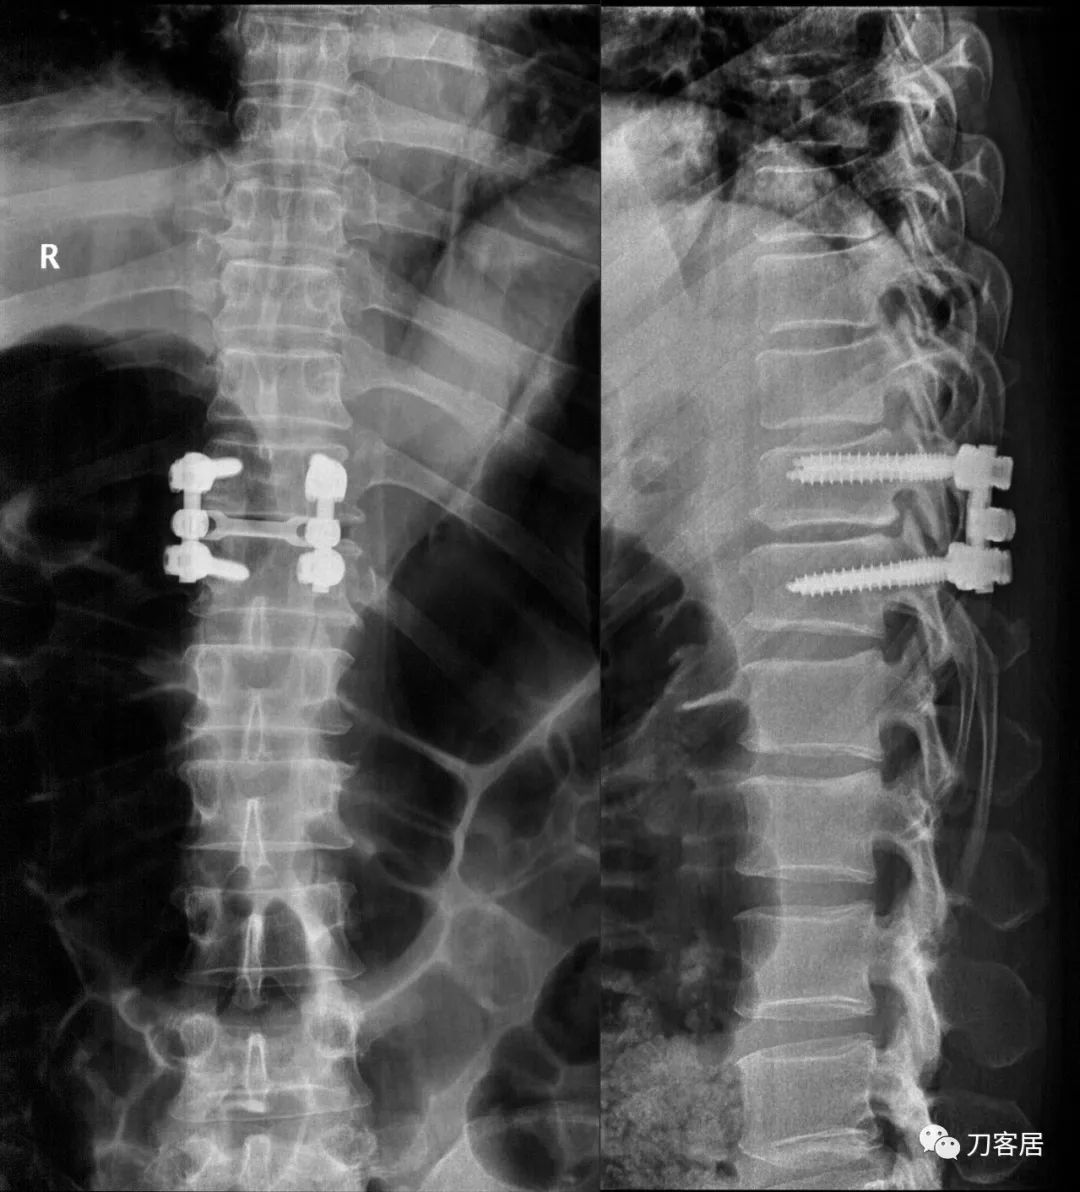

患者及家属决定手术,于2022年9月6日,在全麻下给该患者做了后路胸11-胸12椎板切除减压、植骨融合内固定术。

图26. 20220908术后胸腰椎正侧位X线片。

术后住院期间,患者诉双下肢不适症状已有明显缓解,双足背伸力量也较术前明显好转。